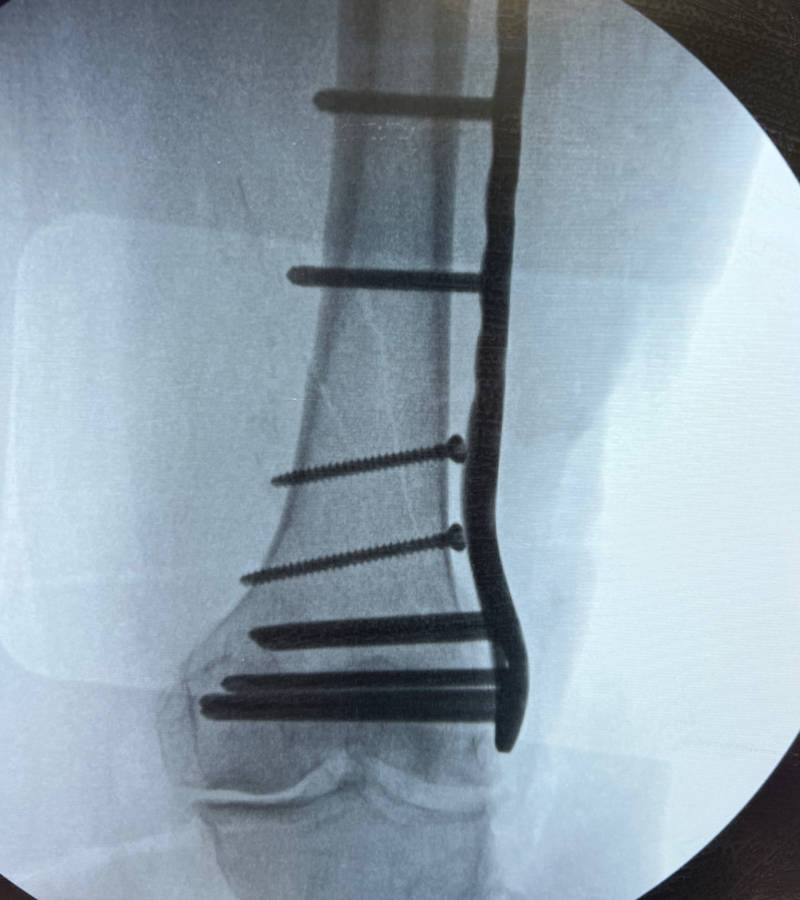

Internal and External Fixation Techniques

Internal Fixation:

This involves using specialized implants like plates, screws, rods (intramedullary nails), or wires to stabilize the broken bone fragments from within. These devices hold the bone in proper alignment while it heals.

Complex Fracture Reconstruction and Non-Union Treatment

Some fractures are particularly challenging, such as those involving multiple fragments, significant bone loss, or those that fail to heal (non-unions). Dr. Arroyo has extensive experience in complex fracture reconstruction, utilizing advanced techniques like bone grafting, specialized plating systems, and biologic agents to salvage limbs and restore function in even the most difficult cases.